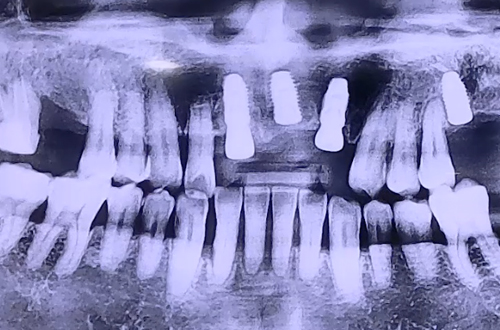

BEFORE

앞 치아들이 많이 흔들리는 상태로 내원하신 환자분입니다.

앞니 3개 중 한 개는 이미 많이 흔들리다 집에서 저절로 빠졌다고 하셨는데요.

정확한 치아 상태를 알기 위해 CT검진을 해 보니,

입천장 쪽 잇몸의 뼈는 괜찮은 편이었지만 바깥쪽 잇몸 뼈들이 완전히 녹아있던 상태였습니다.

잇몸이 약해진 부분, 이가 저절로 빠진 자리와 그 양 옆 흔들림이 있는 2개 치아까지

3개의 앞니 임플란트를 진행하셨고, 빠진 앞니가 많이 보이는 것에 대해서